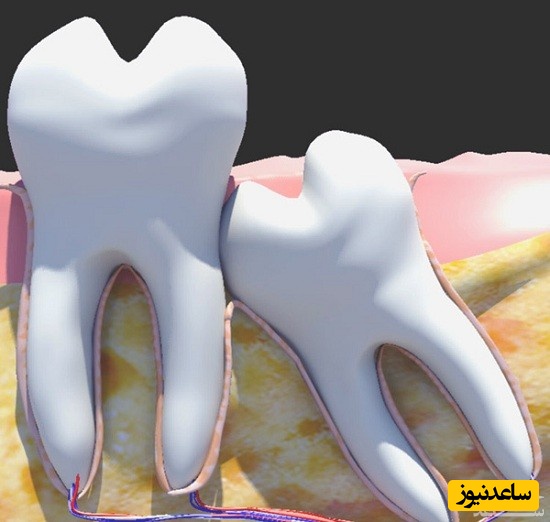

دندان عقل ، یا دقیق تر بگوییم دندان های عقل، شامل ۴ دندان میباشد.۲ دندان عقل در فک بالا و ۲ دندان عقل در فک پایین که در ۴ گوشه دهان قرار دارند. به عبارت دیگر آخرین دندان در هر قوس فکی- به شرط حضور همه دندانها- را دندان عقل گویند. عموما رویش این دندان ها در سنین ۱۷ تا ۲۵ سالگی است. دندانپزشکان اصطلاحا آن را آسیای سوم می نامند. گاهی برخی عوامل مانند ارث، بیماری های دوران کودکی(کم خونی، راشیتیسم )، عدم هماهنگی رشد استخوان فک با اندازه دندان ها و … منجر به نهفته ماندن این دندان ها در داخل فک می شوند. یا این احتمال وجود دارد که به طور ناقص رشد کنند طوری که تنها بخشی از تاج دندان قابل مشاهده باشد که در این حالت به آن دندان عقل نیمه نهفته گفته می شود. متخصصان دندانپزشکی آمریکایی معتقدند که دندان عقل را تنها زمانی که منجر به بروز مشکل و ناراحتی شود، باید کشید زیرا نگه داشتن ان در این صورت عاقلانه نیست.

تاثیر رویش دندان عقل در به هم ریختگى سایر دندانها

همان طور که پیش از این گفتیم بسیاری تصور می کنند که بی نظمی دندان ها به دلیل رویش دندان های عقل و فشار وارد بر دندان های جلو تر ایجاد می شود. بر همین مبنا توصیه می کنند، چه افراد عادی (برای پیشگیری از به هم ریختگی دندان ها) و چه بیماران پس از انجام ارتودنسی، دندان های عقل خود را از دهان خارج کنند. اما باید بدانید در بسیاری از تحقیقات، خلاف این موضوع ثابت شده است. تنها در موارد نادری فشار دندان های عقل، منجر به بی نظمی و جا به جایی دندان های جلوتر شده است آن هم در زمان هایی رخ داده است که دندان های عقل، افقی یا با زاویه ای خاص رشد کرده اند اما بروز بی نظمی دندانی در دایره گسترده ای از انسان ها مشاهده می شود. حتی در بسیاری از افراد که به صورت مادرزادی فاقد دندان های عقل هستند نیز بهم ریختگی دندانی مشاهده شده است. پس نباید دندان های عقل را عامل عمده ای برای بی نظمی دندان ها بدانیم.